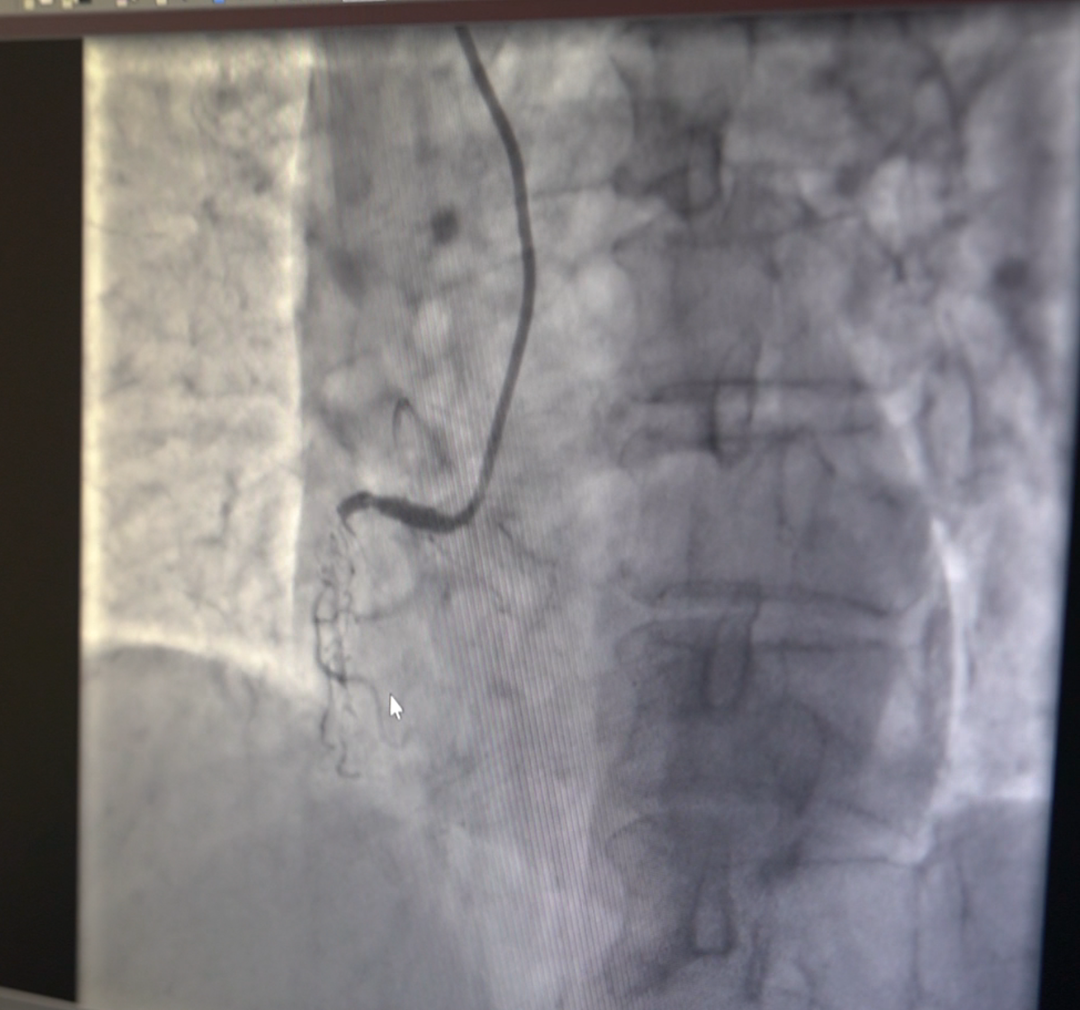

然而,术前检查却发现了更棘手的问题——人的心脏有 3 根冠状动脉,而刘奶奶的 2 根冠状动脉都「堵」了,狭窄程度高达 95% 以上,属于冠心病的极高危病人。

单纯从心脏病的角度来说,像刘奶奶这种高龄复杂冠脉病变的患者,通常在血流动力学(ECMO)的支持下,分次进行介入手术,先开通一支血管,让她的心脏功能恢复半年,再开通另一支狭窄的血管,预计耗时 1 年。

经综合评估,心脏病院执行院长李伟杰冒着巨大的风险,仅用一次手术开通 2 根闭塞的血管,置入 5 根支架,最大限度缩短了患者术后双抗治疗的时间,为后续骨科手术争取了宝贵窗口。